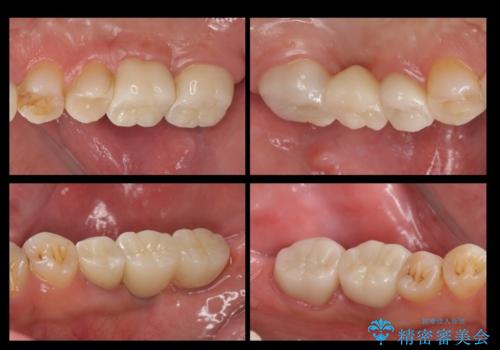

短期間で歯並びをきれいにしたい セラミックでかぶせる治療でも良い

- 短期間で歯並びを治したいとのこと。期間が短ければセラミックでかぶせる治療できれいにするのでも構わない。虫歯の治療もすべてお願いしたいとのことでした。

右下の奥歯は残せない可能性を説明しました。

また、歯並びの矯正をするのではなければ、右上の八重歯は、犬歯を抜くか、奥に入っている歯を抜くかになるとお伝えしました。結果、根の長い犬歯を残して右上の前歯を抜歯しブリッジにしました。また、前歯の神経は極力取らないで治療を行いました。(結果神経を取る治療は前歯には行っておりません)

右下奥歯二本はインプラントにしました。(横浜桜木町歯科院長 大元先生による)

また、銀歯はすべてやり直しを行い、セラミックでやり替えを行いました。

前歯の治療を先に行い、見た目を改善した後、奥歯の治療を行いました。